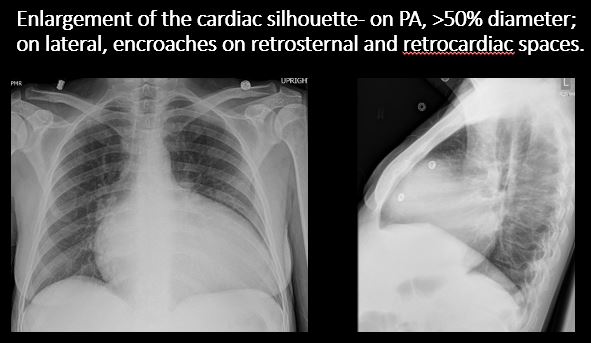

Info Images Findings Impression Reco/Acuity Case Images View Images / Launch Visage Case Notes History 69 yo female with chest pain Exam 2 view chest Prior Study None Dicom View Reference Material